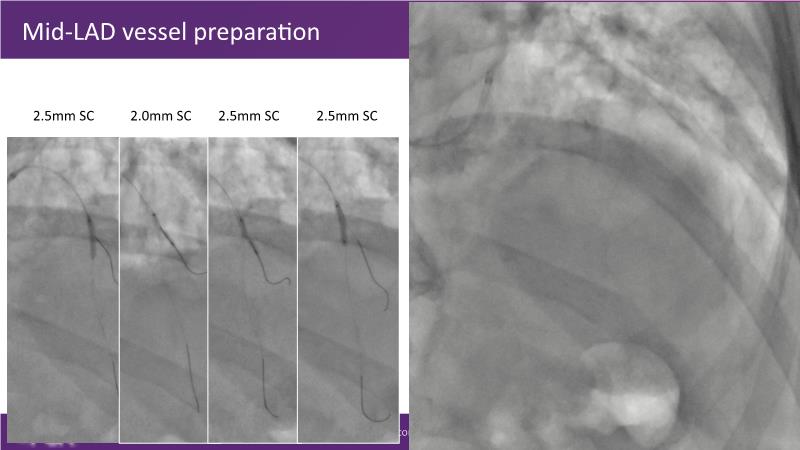

Through the study of two cases, this session examines the need for stenting bifurcation lesions and the role of DEB technology in avoiding stent-related complications in long diffuse disease. It emphasizes the benefits of SELUTION SLR balloons for de novo lesions, discussing how sustained limus release technology can broaden DEB indications and reduce metal usage, understanding the limitations of DES and the emerging role of DEB with sustained limus release, and learning how to identify dissections that can be left unstented.